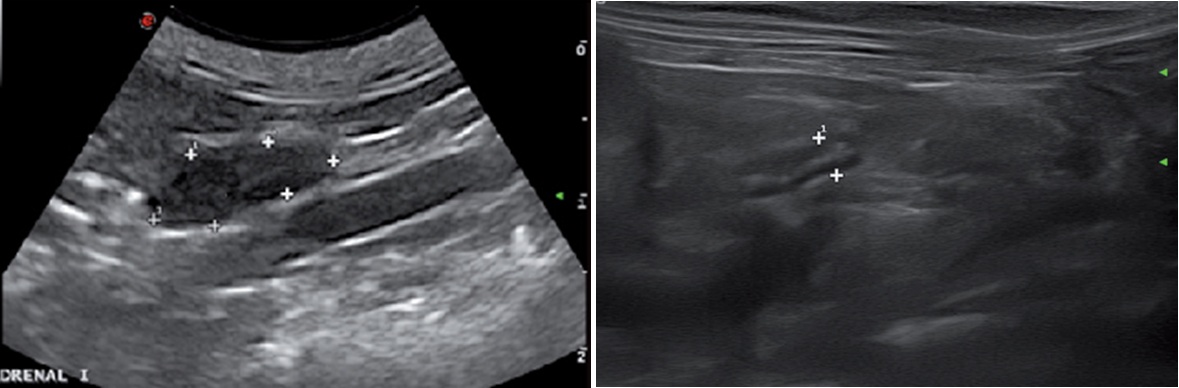

4. 실습을 통한 데일리벳 커뮤니티의 측정

실습을 통하여 데일리벳 커뮤니티의 부신을 관찰하고 측정한 그림입니다(그림 4).

데일리벳 커뮤니티에서는 좌측 부신은 대동맥에서 신장동맥보다는 전장간막동맥을 이정표로 하면 쉽게 찾으며, 우측 부신은 우측 신장의 약간 앞쪽 위치의 CVC에서 찾으면 쉽게 찾게 됩니다(7).